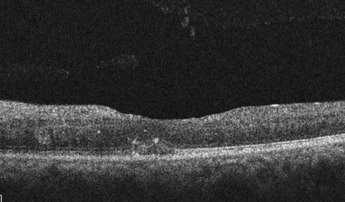

The patient was alert and oriented to time and place. Corrected Snellen visual acuity was 20/20 in the right eye and 20/125 with no pinhole improvement in the left eye. Pupils were equal, round, and reactive to light with no relative afferent pupillary defect in either eye. Extraocular motilities were full in all gazes and confrontation visual fields were full to finger count in both eyes. Slit-lamp examination of the anterior segment was unremarkable in both eyes. Intraocular pressure measured 13 mm Hg in the right eye and 13 mm Hg in the left eye. The patient’s blood pressure was 134/87 mm Hg in-office. The dilated fundus examination was normal in the right eye (Figure 1). Fundus examination of the left eye demonstrated a swollen optic nerve, scattered cotton wool spots, intraretinal hemorrhages throughout the posterior segment, dilated and tortuous veins, and retinal whitening and inner retinal edema in the area of the cilioretinal artery (Figure 2). Neovascularization of the retina and optic nerve was not observed. Fundus photography and Zeiss CIRRUS spectral domain optical coherence tomography were completed. Optical coherence tomography showed hyperreflectivity and thickening of inner retinal layers and loss of inner retinal layer differentiation (Figure 3). The patient was diagnosed with a concurrent central retinal vein occlusion and a cilioretinal artery occlusion in the left eye.

A close-up of a medical image AI-generated content may be incorrect.

Figure 3.Optical coherence tomography of the left eye macula at initial presentation showing hyperreflectivity and thickening of inner retinal layers and loss of inner retinal layer differentiation in the acute stages of the cilioretinal artery occlusion.